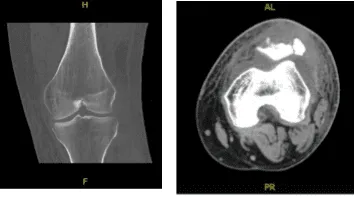

A result for CT SCAN on Left knee was presented and shown comminuted displaced fracture of the patella with new fractures not seen on previous examination status post-surgery. Thickened appearance of the quadriceps tendon, there is excluded.

CT – Left Knee Contrast

Left Knee X-ray Complete with Patella

Patient checked in for a follow up visit after a month and saw significant improvement on his knee. Results for the X-ray were presented and showed revision of the fractured patella with no instrumentations.

Since prior examination noted the presence of a 1.4 cm cystic lesion in the anterior aspect of the medial patella, dislocation has been developed since prior examination.